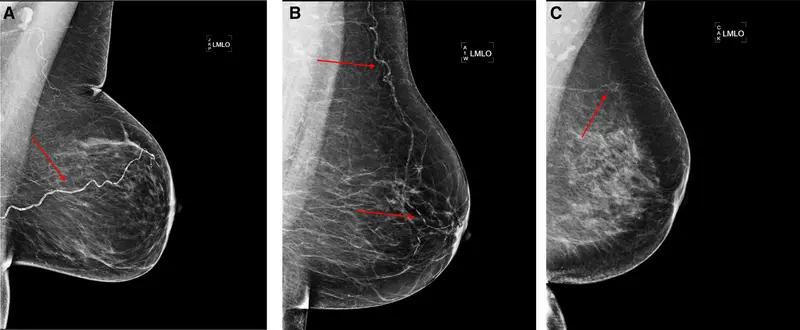

Can Contrast-Enhanced Mammography Offer a Viable Option for Pre-Op Assessment of Pathologic Nipple Involvement?